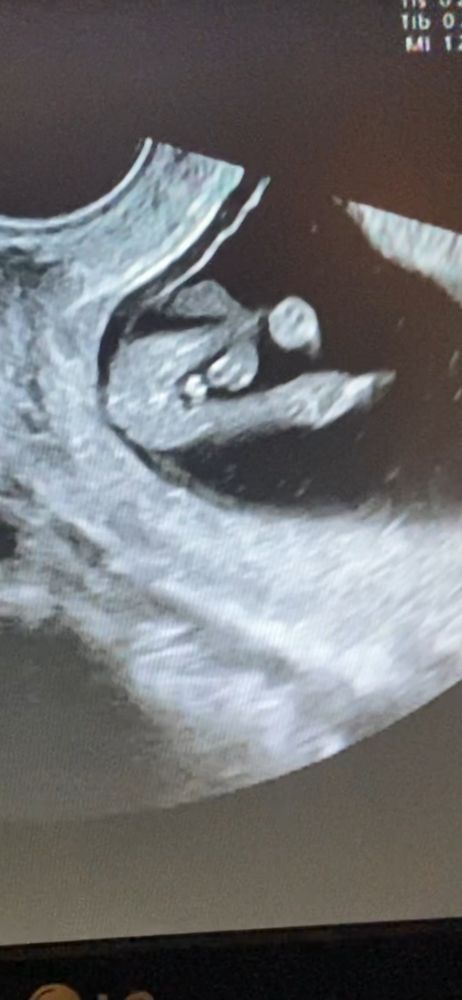

Девочка или мальчик 🤔❤️💜💙

Yana, у девочек вид кофейного зерна между ножек, тут явные очертания мошонки

У меня с такого ракурса другие очертания были, очевидно девочковые) полагаю, что у Вас мальчик.

У меня на 16нед такая же картинка была, пацан.

Анюта, 13 я неделя

Елена, я думала больше. На 13й неделе пол смотрят в профиль, а не между ножек, между ножек не информативно. Но вообще странно, на снимке явная мошонка, хотя для нее рано.

Чашка утреннего кофе, наших смотрели между ножек. Мошонки не было видно, зато они оба гордо продемонстрировали члены)) А у автора, скорее всего, девчоночка))

А вы ещё сомневаетесь?) Мальчик ж явно)

Чашка утреннего кофе, нам узистка сказала что у нас вероятнее всего девочка😅 Вот мы и сомневаемся 🧐

Елена, у вас странная узистка) у девочек там по-другому)